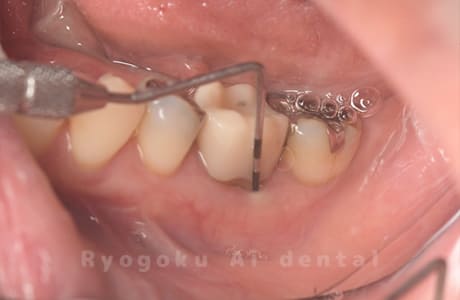

Case05

-

術後2ヶ月

- 原因

- 右下6番近心根パーフォーレーション

- 治療内容

- 外科的パーフォレーションリカバリー治療

- 治療費用

- ¥66,000

右下の奥から2番目の歯に穴が空いており、腫れが引かず、他院で抜歯と診断された患者様です。被せ物を外さずに、穴が空いている部分に外科的にアクセスし、その部分を修復手術を行いました。治療後も再発せず、経過良好です。

<リスク・副作用>

手術後は痛み、腫れ、痺れ、青あざなどの副作用が生じます。痛みは痛み止めを処方しますが、腫れ、青あざは1週間程度生じる場合があります。また、部位によっては神経の走行が複雑で、痺れが残り、長期的にお薬を処方する場合があります。